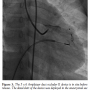

An arterio-venous loop was made, and a 6 Fr shuttle delivery sheath (Cook Medical) was advanced over this wire from the venous end. However, the sheath could not be negotiated into the fistula from the right ventricular end (Figure 2). Hence, through the same delivery sheath, a 5 Fr right Judkin’s guiding catheter was introduced into the fistula. A 5 x 6 ADO II device was loaded and then advanced into the Judkin’s catheter and the distal skirt of the device was deployed in the aneurysmal part of the fistula.

The guiding catheter was then withdrawn up to the right ventricular aspect of the fistula and the proximal retention skirt was released in the right ventricular end of the fistula (Figure 3). Repeat angiogram showed good position of the device with no residual shunt and better opacification of the coronary arteries (Figure 4). No complication occurred during or after the procedure. Electrocardiogram showed no changes. The patient was put on aspirin 5 mg/kg/day for 3 months. She was examined after 3 and 12 months and was asymptomatic with no murmur on clinical examination, and no residual shunt on echocardiogram.